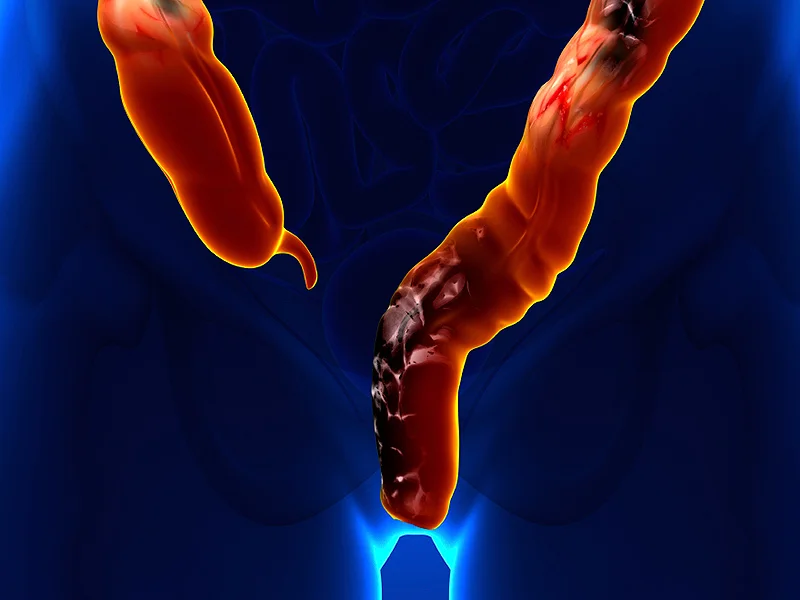

Рак 3 Стадии ФотоВыберите Ваш пол👨 👉🏻👉🏻👉🏻МУЖЧИНА👈🏻👈🏻👈🏻👩🦱 👉🏻👉🏻👉🏻ЖЕНЩИНА👈🏻👈🏻👈🏻Рак 3 Стадии Фото (143 фото)